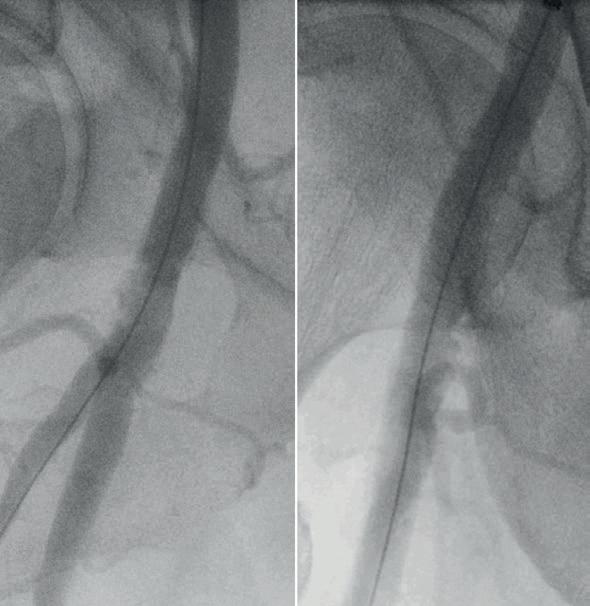

Here we present the case of an 84-year-

old man with severe disabling claudication of the right lower limb due to a highly calcified stenosis of the CFA. He has no major comorbidities and lives alone at home. Duplex scan evaluation revealed a tight stenosis of the common femoral artery with a heavily calcified circumferential lesion and a peak systolic velocity of 380cm/s. The duplex waveform was monophasic below the lesion. A non-significant iliac stenosis and severe lesions of the distal arteries were also evident. A computed tomography angiography (CTA) scan confirmed a highly calcified stenosis of the CFA sparing the bifurcation (Figure 1). The CFA diameter was measured as 7.4mm. The contralateral CFA presented as calcified but not stenosed and thus suitable for puncture. An endovascular repair of the CFA using an IVL preparation was decided as our preferred strategy.

The procedure was scheduled as a sameday discharge intervention and performed under local anaesthesia with sedation in an operating room using standard fluoroscopic guidance with a mobile C-arm. A 7Fr 45cm sheath was brought from the contralateral femoral artery with a crossover technique. The initial angiography showed the lesion, which appeared to be a near occlusion of the CFA (Figure 2), with a low flow in the profunda femoris artery (PFA). A 0.014” wire was positioned antegrade in the PFA due to lesion morphology to preserve the bifurcation. An 8x60mm M5+ IVL catheter

(Shockwave Medical) was selected to prepare the lesion. The use of a slightly oversized balloon allows a perfect apposition to the lesion to deliver the sonic pressure waves. Care was given to deliver the pulses using an overlap strategy to bring the sonic waves at different levels of the lesion to fracture the plaque (Figure 3). The fact that the balloon is inflated at a low pressure (four atmospheres) allowed for inflation in the distal portion of the PFA without having the fear of damaging it. A total of 300 pulses was delivered on the lesion to optimise the effect of IVL. The postpreparation angiography was performed with two different incidences (anterior and oblique view) showing a successful preparation. The luminal gain was satisfactory without

significant residual stenosis or dissection. An 8x60mm drug-coated balloon was inflated at eight atmospheres for three minutes as the anti-restenotic therapy. Completion angiography showed a successful procedure with good flow in the CFA, the PFA and the superficial femoral artery (SFA; Figure 4). The patient was discharged home the same day with dual antiplatelet therapy. At six-month follow-up, the patient presented as healthy and could walk without any limitation. Duplex scan evaluation confirmed a satisfactory mid-term result of the procedure without any significant restenosis and a triphasic flow at the level of and below the lesion.

[IVL therapy] modifies the compliance of the vessel by creating microfractures in the plaque, allowing for a controlled expansion with limited complications.”3 4 Figure 3. Care was given to deliver the pulses using an overlap strategy to bring the sonic waves at different levels of the lesion to fracture the plaque